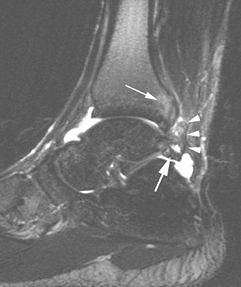

For the injection therapy, a 20- or 23-gauge needle was inserted directly to the abnormal area of the posterior capsule. Then, 40 mg of triamcinolone acetonide and 3 mL of 0.5% bupivacaine hydrochloride were injected into the abnormal tissues. If an os trigoum was present, the needle was moved on to the ossicle.

According to the results, all patients had posterolateral hypoechoic capsule thickening that was nodular and localized to the lateral aspect of the lateral talar process or os trigonum. All 10 patients tolerated the injection procedure with no immediate complications. They also reported ankle improvement after the bupivacaine shot.

![]() |

| Axial sonography image of os trigonum (O) and adjacent fragment (Fr) obtained during injection shows nodular synovitis (asterisk) with needle (arrowheads) placed during infiltration and injection. Further infiltration was performed around fragments. Robinson P and Bollen SR, "Posterior Ankle Impingement in Professional Soccer Players: Effectiveness of Sonographically Guided Therapy" (AJR 2006; 187:W53-W58). |

The median follow-up time was 26 months for all players. At this juncture, eight out of 10 patients with posterolateral synovitis and no os trigonum had no residual or recurrent symptoms. The remaining two players who did have posterolateral synovitis and os trigonum on imaging experienced a recurrence of symptoms and underwent repeat injection with ultrasound guidance. One player remained pain-free after the second session; the other required endoscopic resection.